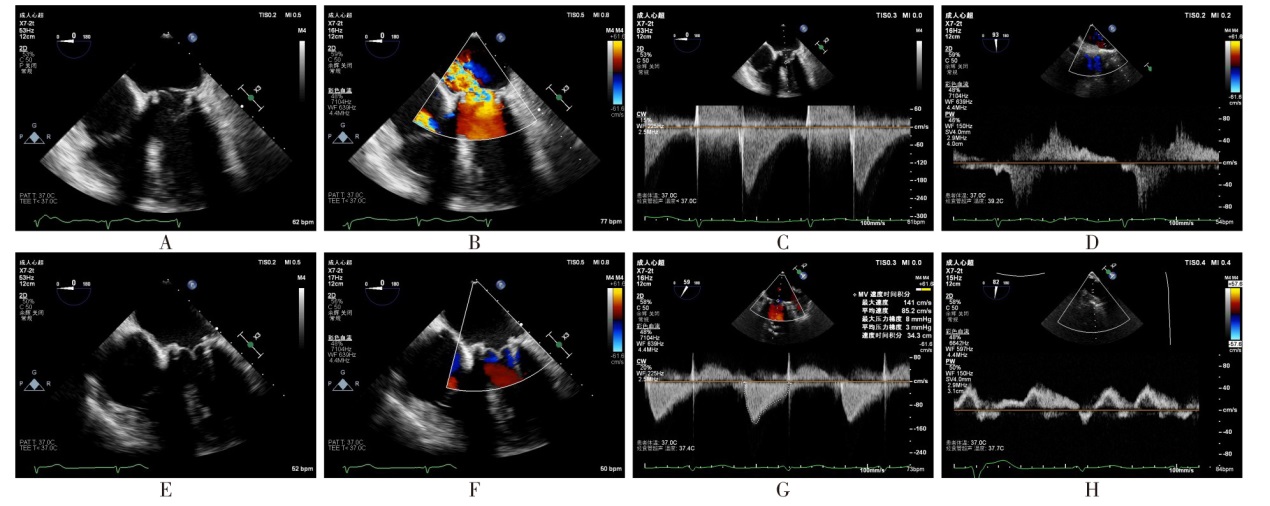

目的 评估经导管二尖瓣“瓣中瓣”置换术(ViV-TMVR)治疗人工二尖瓣生物瓣衰败的安全性和有效性。方法 选取17例因二尖瓣生物瓣衰败需行ViV-TMVR的患者,收集患者的年龄、性别、体质量指数(BMI)、二尖瓣生物瓣使用年限,合并症(高血压、冠心病、陈旧性脑梗死、心房颤动、糖尿病),美国纽约心脏病学会(NYHA)心功能分级;术前超声心动图评估左心室舒张末期内径(LVEDD)、右心房内径(RA)、肺动脉收缩压(PASP)、左心室射血分数(LVEF),二尖瓣生物瓣衰败类型,二尖瓣生物瓣反流程度、狭窄程度,术前生物瓣峰值流速、平均跨瓣压差,三尖瓣反流程度;美国胸外科医师协会(STS)评分;术中穿刺路径、瓣膜类型、术中并发症、手术时间、术后即刻经食管超声心动图(TEE)评估(瓣中瓣峰值流速、瓣中瓣平均跨瓣压差、瓣中瓣反流或瓣周反流);术后进入重症监护室(ICU)/心血管内科重症监护室(CCU)的时间,术后住院时间,以及术后30 d超声心动图复查结果,NYHA心功能分级。根据使用瓣膜不同分为国产纽脉瓣膜组(国产组,10例)与进口爱德华瓣膜组(进口组,7例)。分析ViV-TMVR的安全性和有效性,并对比国产瓣膜和进口瓣膜的效果。结果 17例患者均成功通过穿刺房间隔途径接受ViV-TMVR治疗,且未发生严重并发症,术后30 d再住院率为0。国产组与进口组手术时间、瓣中瓣瓣周轻度反流、术后即刻及术后30 d瓣中瓣峰值流速、术后即刻及术后30 d瓣中瓣平均跨瓣压差、术后ICU/CCU监护时间、术后住院时间,术后30 d NYHA心功能Ⅲ—Ⅳ级患者占比差异无统计学意义。术后30 d随访中1例患者因脑出血死亡,主要不良心血管事件(MACE)为脑出血1例。相较于术前,术后即刻及术后30 d瓣中瓣峰值流速、瓣中瓣平均跨瓣压差、LVEF、PASP下降;相较于术后即刻,术后30 d瓣中瓣峰值流速、平均跨瓣压差升高(P<0.01),LVEF、PASP差异无统计学意义。结论 经房间隔穿刺ViV-TMVR对于生物瓣衰败患者短期安全且有效,且国产瓣膜与进口瓣膜疗效相当。

Objective To evaluate the safety and efficacy of transcatheter mitral valve-in-valve replacement (ViV-TMVR) in the treatment of bioprosthetic mitral valve failure. Methods Seventeen patients with bioprosthetic mitral valve failure who required ViV-TMVR were selected. Preoperative data including age, gender, body mass index (BMI), usage time of bioprosthetic mitral valve, comorbidities (hypertension, coronary heart disease, old cerebral infarction, atrial fibrillation and diabetes) and New York Heart Association (NYHA) functional class were recorded, and left ventricular end-diastolic diameter (LVEDD), right atrial diameter (RA), pulmonary artery systolic pressure (PASP), left ventricular ejection fraction (LVEF), type of bioprosthetic mitral valve failure, degree of bioprosthetic mitral valve regurgitation and stenosis, peak velocity and mean transvalvular pressure gradient of the bioprosthetic mitral valve, and Society of Thoracic Surgeons (STS) score were also collected. Intraoperative data included puncture route, valve type, intraoperative complications, operation time and immediate postoperative transesophageal echocardiography (TEE) assessment (peak velocity and mean transvalvular pressure gradient of the valve-in-valve, valve-in-valve regurgitation or paravalvular regurgitation) were collected. Postoperative data included time in the intensive care unit (ICU)/cardiovascular intensive care unit (CCU), total postoperative hospital stay and 30-day postoperative echocardiographic results and NYHA functional class were recorded. Patients were divided into the domestic NewMed valve group (10 cases) and the imported Edwards valve group (7 cases) based on the type of valve used. The safety and efficacy of ViV-TMVR were analyzed, and the efficacy of domestic valves and imported valves was compared. Results All 17 patients successfully underwent ViV-TMVR via the transseptal approach without serious complications, and the 30-day readmission rate was 0%. There were no significant differences in operation time of domestic valves and imported valves, mild paravalvular regurgitation of the valve-in-valve, peak velocity and mean transvalvular pressure gradient of the valve-in-valve immediately after surgery and at 30-day postoperatively, time in ICU/CCU, total postoperative hospital stay and the proportion of patients with NYHA functional class Ⅲ-Ⅳ at 30-day postoperatively between the domestic valve group and the imported valve group. During the 30-day follow-up, one patient died of cerebral hemorrhage, and one patient had major adverse cardiovascular events (MACE, cerebral hemorrhage). Compared with before the operation, the peak velocity and mean transvalvular pressure gradient of the valve-in-valve, LVEF, and PASP decreased immediately after surgery and at 30 days after surgery. Compared with immediately after surgery, the peak velocity and mean transvalvular pressure gradient of the valve-in-valve increased at 30 days postoperatively (P < 0.01), while there were no significant differences in LVEF and PASP. Conclusion Transseptal ViV-TMVR is safe and effective in the short term for patients with bioprosthetic mitral valve failure who are at high risk of re-thoracotomy, and the efficacy of domestic valves is comparable to that of imported valves.